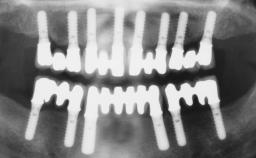

Conventional Loading of Six Implants in the Mandible and Final Restoration with a Full-Arch Metal-Ceramic FDP

A 68-year-old, completely edentulous male patient presented for evaluation and treatment options. He reported excellent general health and was taking no regular medication. He had been edentulous for approximately 12 years, having lost his teeth to periodontal disease and dental caries. The patient’s chief complaint was incompetent function. His secondary concerns included his appearance and the desire for a predictable outcome. He attributed his reduced functional capacity to his lower complete denture, which he described as poor. He was particularly concerned with the denture’s instability and poor fit. In general terms, he was satisfied with the maxillary complete prosthesis. The maxillary prosthesis was characterized by adequate retention, stability, and support, although the fit was considered less than ideal.

# of Implants 6

Type of Implants One-Piece

Defining Characteristics Fully edentulous lower jaw to be rehabilitated with an implant-borne fixed dental prosthesis

Retention Screw-retained, with 4 or more splinted implants Screw-retained, with 4 or more splinted implants